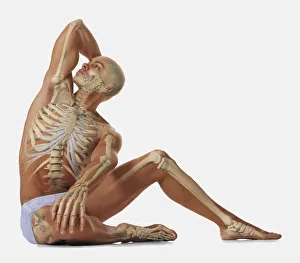

The scapula, also known as the shoulder blade, is a crucial bone in our body that plays a significant role in our mobility and stability. It forms part of the pectoral girdle and connects the upper arm to the thorax. When we examine diagrams of the bones of the hand and arm, we can see how intricately connected they are to the scapula. This connection allows us to perform various movements with precision and control. In an anterior view total shoulder joint repair image, we witness medical advancements aimed at restoring functionality to this vital joint. The intricate procedure highlights just how important it is to maintain a healthy scapula for optimal movement. Shoulder muscles artwork showcases their attachment points on the scapula, emphasizing their role in providing strength and stability during physical activities. Understanding these muscles helps us appreciate their contribution to everyday tasks like lifting or throwing. A front view of female anatomy highlighting the endocrine system reminds us that even though not directly related to the scapula, every part of our body works together harmoniously. Hormones secreted by glands within this system influence bone health and development. An anterior view of human skeletal system with labels gives us a comprehensive understanding of where exactly our scapula fits into this complex framework. It serves as an anchor point for numerous ligaments and tendons essential for proper functioning. Pictograms on an ox scapula depict ancient rituals performed to ward off danger—a testament to how cultures throughout history recognized its significance beyond mere anatomy. These artifacts remind us that humans have long understood its importance in daily life. The skeleton of an eagle after Milne-Edwards engraving demonstrates nature's adaptation at its finest—the bird's wingspan relies heavily on strong shoulder blades (scapulas) allowing it effortless flight through vast skies. Haydon's Curtius engraving captures another artistic representation showcasing human form—this time focusing on muscular structure including the scapula.